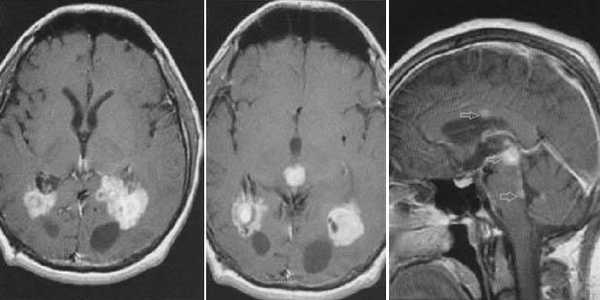

Пинеоцитома. На Т2 ВИ опухоль состоит из двух участков разной интенсивности МР-сигнала: высокой в передних отделах и низкой в задних. Четкость и линейность перехода свидетельствует о кистозном характере строения опухоли. Различия интенсивности МР-сигнала от жидкости в передних и задних отделах опухоли обусловлены эффектом «седиментации» белковых компонентов (вероятнее компонентов крови), опускающихся вниз при положении головы пациента на затылке.

Пинеоцитома. МРТ в режиме Т2 и Т1 выявляется солидного строения опухоль задних отделов III желудочка мозга. На фоне в/в контрастирования определяется выраженный и достаточно гомогенный характер контрастирования опухоли.

Пинеобластома. В режиме Т2 и Т1 выявляется опухоль задних отделов III желудочка мозга с развитием окклюзионной гидроцефалии. В строме опухоли небольшой участок подострого кровоизлияния. После в/в контрастирования опухоль интенсивно и достаточно гомогенно накапливает контрастирующее вещество.